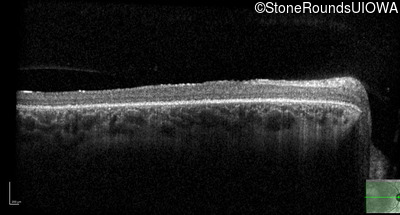

Optical Coherence Tomography - Right - 20/100 -1 sc

Exemplar / OCT Stack

OCT Stack